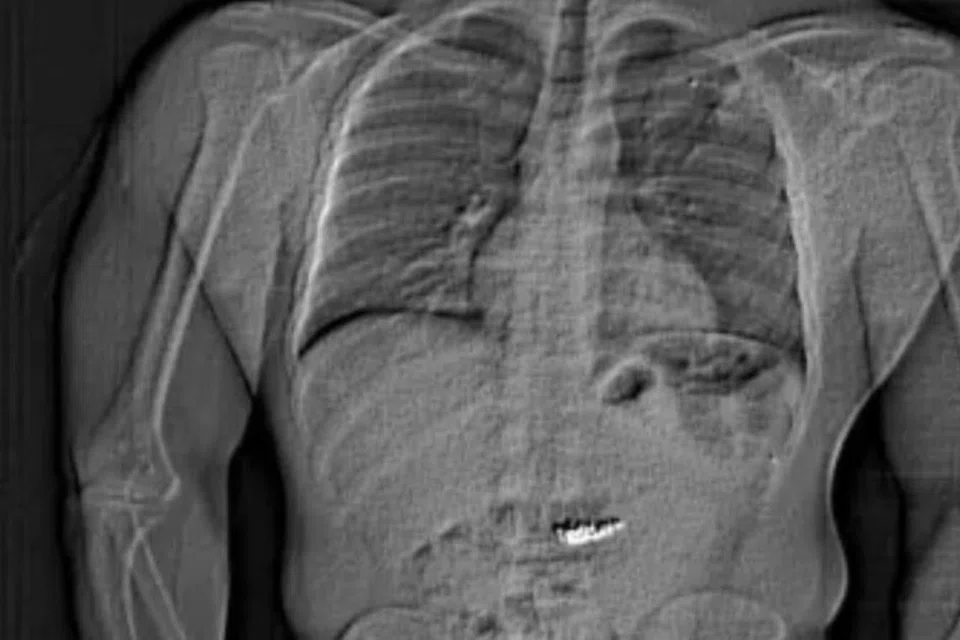

பின்னர் அவர் ஊடுகதிர் ( X-ray) பரிசோதனைக்கு உட்படுத்தப்பட்டார். அதில் அவரது வயிற்றுப்பகுதியில் நகை இருந்தது தெளிவாகத் தெரிந்தது.